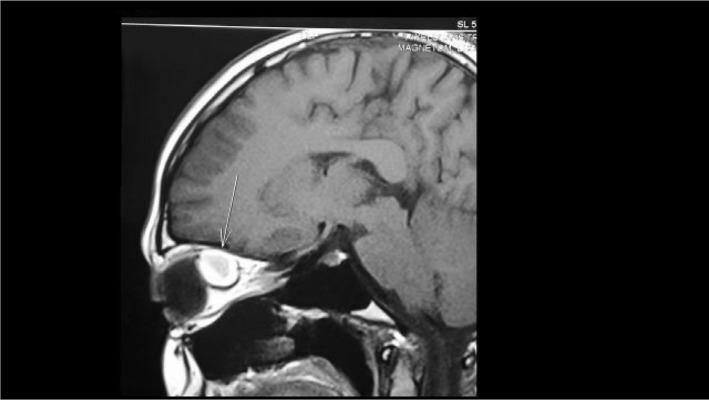

We report an unusual presentation of an orbital cavernous hemangioma in a 26-year-old female, who noted sudden redness and swelling of the left eye (LE) on waking up. At presentation, upper eyelid edema with periorbital ecchymosis and subconjunctival hemorrhage were noted in the LE. Although there was transient symptomatic relief with topical medications, blurring of vision developed in the LE. When seen 10 days later, the patient's LE showed axial proptosis. Magnetic resonance imaging revealed an intraconal soft tissue mass in the superomedial quadrant of the left orbit. Superior orbitotomy with mass excision was done; histopathological examination of the excised mass revealed a cavernous hemangioma. The patient had complete visual recovery following surgery. To our knowledge, an acute presentation of an orbital cavernous hemangioma with subconjunctival hemorrhage and periorbital ecchymosis has not previously been reported.

摘要

我们报告了一例26岁女性眼眶海绵状血管瘤的不寻常表现,该患者醒来时发现左眼突然发红肿胀。就诊时,左眼可见上睑水肿伴眶周瘀斑及结膜下出血。尽管局部用药后症状有短暂缓解,但左眼出现视力模糊。10天后复诊时,患者左眼出现轴性眼球突出。磁共振成像显示左眼眶上内侧象限锥内软组织肿块。行眶上切开术并切除肿块;切除肿块的组织病理学检查显示为海绵状血管瘤。患者术后视力完全恢复。据我们所知,眼眶海绵状血管瘤伴结膜下出血和眶周瘀斑的急性表现此前未见报道。